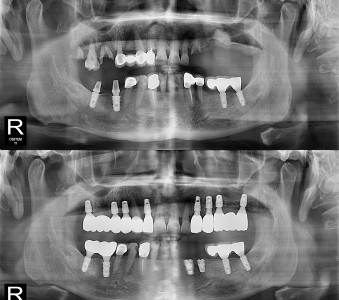

오스템 임플란트 프리미엄 BA 등급 사용

같은 오스템이라도 등급이 다릅니다. 더 빠른 골유착을 위해 프리미엄 등급을 사용합니다.

전 과목을 한 곳에서! 통합치의학과 전문의 통합진료

통합치의학과 전문의가 상주하여 임플란트·교정·보철·심미·충치·소아치료 등 전 과목을 한 곳에서 통합적인 진료가 가능합니다.

결과로 증명합니다.

국제모아치과의

실제 임상 증례